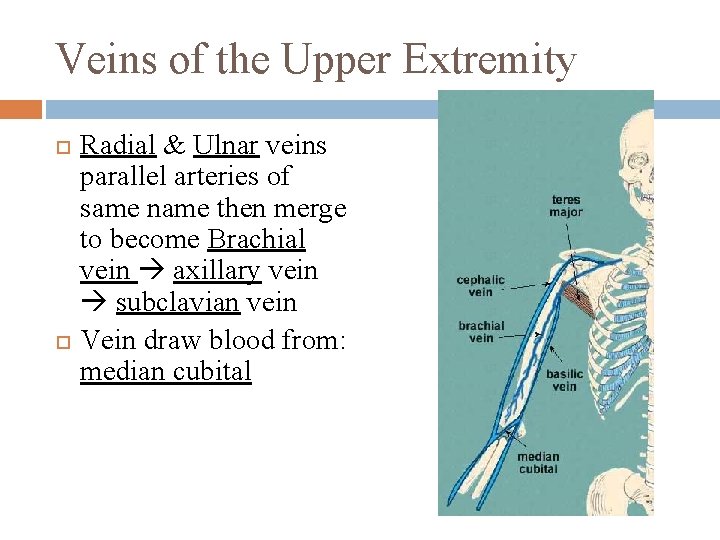

Veins of the Upper Extremity Radial & Ulnar veins parallel arteries of same name then merge to become Brachial vein axillary vein subclavian vein Vein draw blood from: median cubital